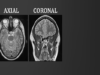

Lung Abscess Mediube Subscribe Subscribed 3 1173 videos 0% 48 Views 0 Likes 2025-01-22 PulmonologyImagingX-Ray By Mediube 0 Comments (بازدید 48 بار, بازدیدهای امروز 1 ) Show more PREV Introduction to MRI of the brain Mediube 2025-01-20 NEXT Lung Abscess Mediube 2025-01-22 You might be interested in 0 What Happens During a CT Lung Scan Mediube 2024-06-06 0 Using the Bougie for Endotracheal Intubation Mediube 2025-03-10 0 Abdominal X-Rays Made Easy Mediube 2024-09-30 0 Signs of asthma Mediube 2024-05-21 0 Black fungus and corona Mediube 2024-01-11 0 Complete Breath sounds- Normal-Abnormal Lung Sounds, Types Conditions Mediube 2024-05-16 0 What is a Tension Pneumothorax? | Lecturio Emergency Medicine Mediube 2024-04-18 0 How to identify normal lung anatomy on chest CT Mediube 2024-06-06 0 Lung Cancer Treatment Mediube 2024-09-25 0 Intro to Head CT Part III_ Tumor and Infection Mediube 2025-06-07 0 How Can I Spot an Ectopic Pregnancy With Ultrasound. Mediube 2024-07-06 0 Ace Your Respiratory Examination OSCE With This Clinical Skills Mediube 2024-12-23 LEAVE YOUR COMMENT Cancel replyYour email address will not be published. Required fields are marked * Save my name, email, and website in this browser for the next time I comment. Δ